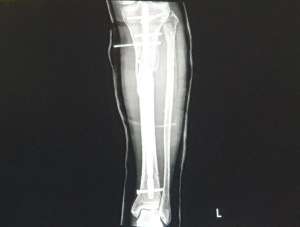

경비골 모두 골절되었는데

경골 만 수술받고, 비골은 비수술이었다.

골절 부위가 무릎 바로 아래이기 때문에 수술시 애를 먹었다.

경골의 부러진 곳을 이어주는 금속판을 대고

나사로 조이는 수술이었는데

수술한 후 살갗에는 핀이 2개 돌출되었다.